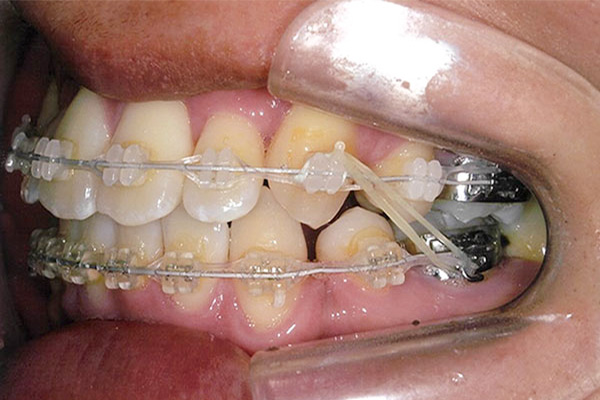

6ヶ月後